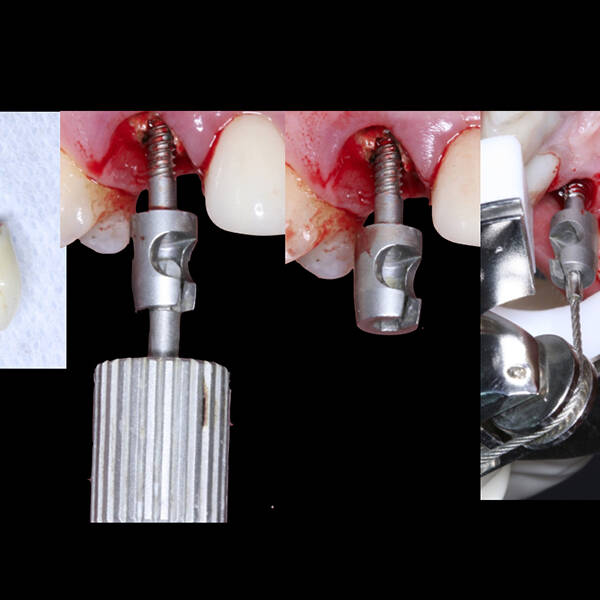

- Cirurgia de Instalação dos Implantes: Os implantes são fixados no osso maxilar ou mandibular, proporcionando uma base sólida para a prótese.

- Fixação da Prótese: Em até 72 horas após a cirurgia, a prótese provisória é instalada, permitindo que o paciente recupere a funcionalidade e a estética imediatamente.